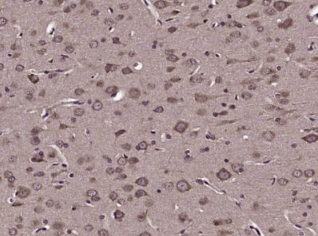

多聚甲醛固定,石蜡包埋(大鼠脑);经柠檬酸钠缓冲液(pH6.0)煮沸15min后获得抗原;用3%过氧化氢阻断内源过氧化物酶20分钟;阻断缓冲液(正常山羊血清)37℃30min;用(Angiotensin II型1A受体)多克隆抗体(未结合)进行抗体孵育。)在1:400在4°C下过夜,然后根据SP试剂盒(兔子)说明和DAB染色进行操作。